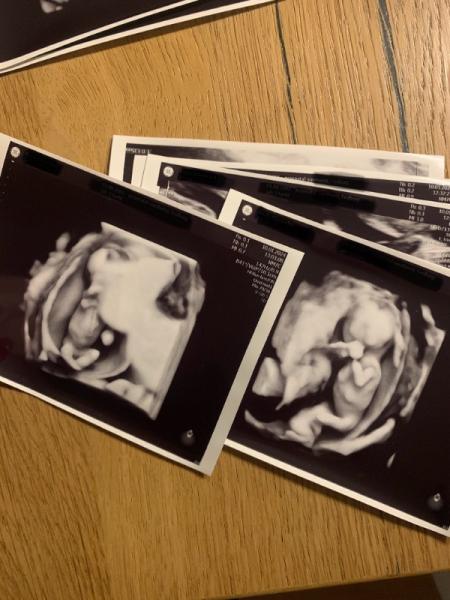

Das war ein langer Tag heute! Am Vormittag waren wir erst beim Makler und dann beim Notar und haben den Kaufvertrag für unser Haus unterschrieben und dann sind wir zur Feindiagnostik gefahren. Nach ewigem warten durften wir unsere kleinen endlich etwas besser kennenlernen. Es scheint so, als wären beide gesund. Baby A hat eine zu dicke Nackenfalte gehabt. Aber sonst keine Auffälligkeiten. Das war bei meiner Tochter damals auch schon so. Mach mir da keinen Kopf drum. Baby A ist auch eher 14+0 und Baby B eher 13+4. Ich heute laut ET 13+4. Sie meinte aber das man bei Zwillingen das Schwangerschaftsalter nach dem größeren Zwilling richtet. Hat aber auch gesagt, sie glaubt, dass sich die beiden einfach auch verzögert eingenistet haben. Wenn der Größenunterschied in Zukunft in etwa so bleibt dann ist alles supi. Und Baby B war ja immer noch schon etwas kleiner. Aber deshalb haben wir dann doch auch noch den Bluttest gemacht. Der war ja dann kostenlos also warum nicht. Eine Geschlechter Tendenz gab es dann auch, Baby A ist wohl ein Junge, da war sie sich recht sicher und Baby B scheint ein Mädchen zu sein In 6 Wochen darf ich auch zur Kontrolle hin. Und jetzt kann ich auch bald den Termin für die Cerclage vereinbaren. Läuft also alles ganz gut würde ich sagen. Anbei noch ein Bildchen. Links ist A und rechts ist B - beide wohl schüchtern